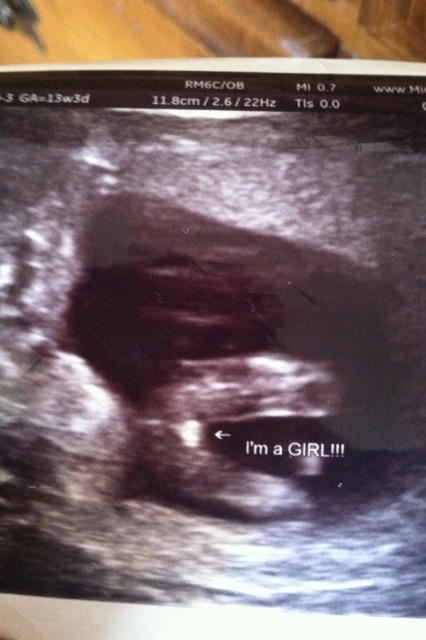

19.1w Attachment 10959 13.3w Attachment 10960

Congratulations on our baby girl!